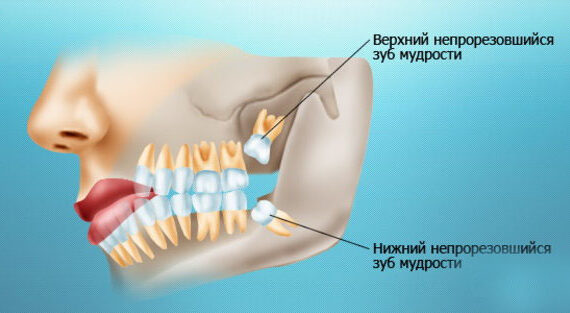

- верхние зубы, не имея антагонистов, выдвинулись вниз (зубоальвеолярное удлинение, т. н. «симптом Попова-Годона»).

- Зубоальвеолярное удлинение в области зубов-антагонистов. Решается: ортодонтическим лечением.

Пару слов об ортодонтии в данной ситуации. Раньше (да и сейчас) некоторые доктора решали вопрос «выдвижения» отдельных зубов очень просто: их депульпировали, стачивали до нужного уровня и покрывали коронками. Но подумайте — согласились бы вы покрыть коронками нормальные, в общем-то, зубы? Я — ни за что. Поэтому я приглашаю ортодонта (в нашей клинике есть замечательный доктор Слива Виктория), мы планируем с ней ортодонтическое лечение: на данный сегмент зубного ряда будут наклеены брекеты, затем, с помощью микровинтов (кортикальная опора), мы проведем интрузию («втягивание») данных зубов в правильное положение. Это займет несколько месяцев, как раз до этапа протезирования.

- Что делать с верхними зубами? Мы уже ответили на данный вопрос. Параллельно с имплантологическим лечением, мы будем проводить интрузию («втягивание») верхних зубов на их правильные места. Этим займется ортодонт Слива Виктория Рандовна.